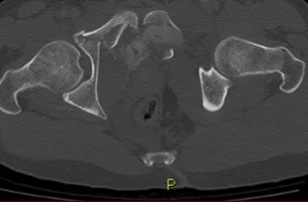

- CT

- routine part of pelvic ring injury evaluation

- better characterization of posterior ring injuries

- helps define comminution and fragment rotation

- visualize position of fracture lines relative to sacral foramina